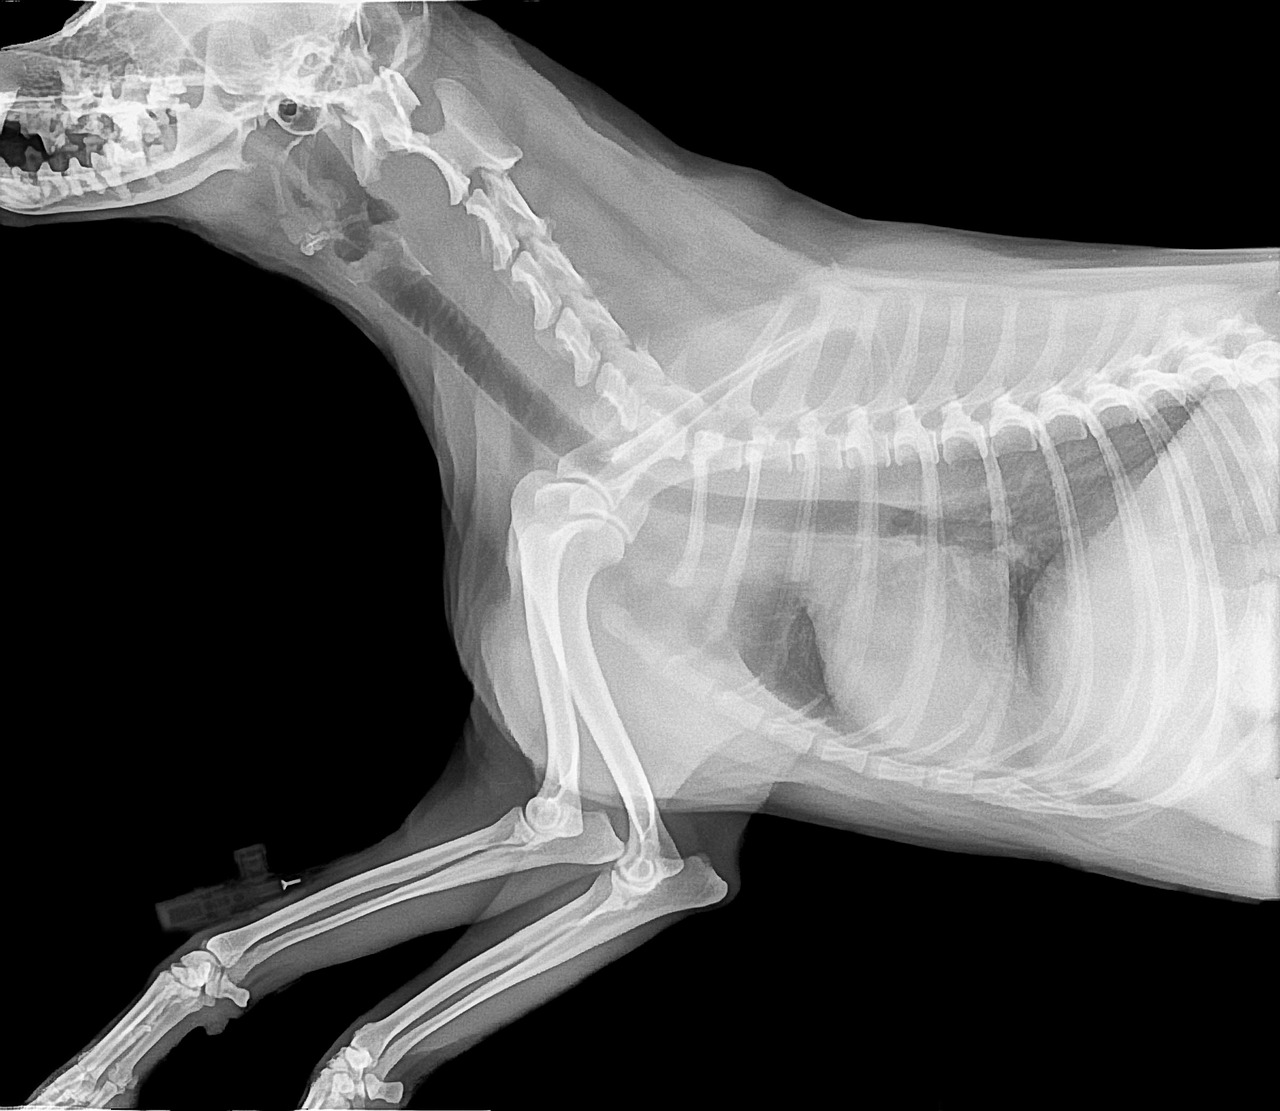

Common Bone Disorders in Dogs and How to Prevent Them

Bone disorders in dogs can significantly impact their quality of life, affecting mobility, behavior, and overall health. One of the most common issues is hip dysplasia, where the hip joint does not fit properly into the hip socket. This malformation can lead to arthritis and severe pain. Osteochondritis dissecans (OCD) is another disorder, often seen in large breeds, where cartilage becomes damaged, affecting joint function. Other examples include luxating patella and bone fractures. These conditions are particularly challenging as they can develop silently over time, making it crucial for dog owners to be vigilant. Regular vet check-ups become essential to catch these issues early on. Maintaining an appropriate weight, providing supportive nutrition, and engaging in moderate exercise are fundamental preventive measures. Dog breeds may have specific predispositions to certain bone disorders, making awareness important. Identifying early symptoms like limping, decreased activity, or reluctant movement should prompt immediate veterinary consultation. Thus, understanding these bone disorders is an essential step towards ensuring your dog’s long-term health and comfort. Through proper preventive care, you can help address and mitigate these common issues.